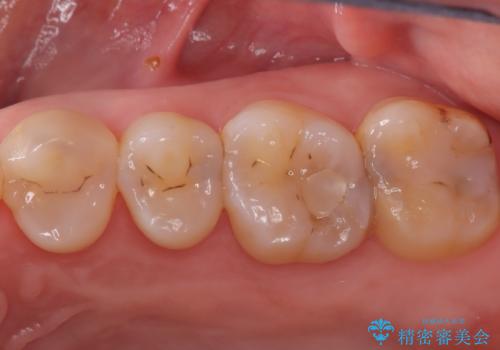

欠けやすい大きなプラスチック充填から、耐久性の高いセラミッククラウンへ

担当医 河口智英